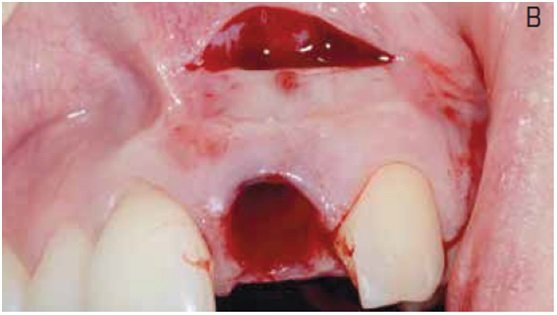

A presença de patologias na região apical de um dente comprometido pode interferir diretamente no tratamento com implantes dentários através da reincidência de infecção, e indiretamente através do trauma necessário para adequada limpeza do sítio infectado. Esse trauma torna-se mais relevante na região anterior maxilar, suscetível à recessão óssea, e recursos que o minimizem estão indicados. Através de um caso clínico, o presente trabalho apresenta o tratamento de uma lesão extensa na região periapical de um incisivo central maxilar com comprometimento da tábua óssea vestibular na região apical.

O tratamento consistiu na extração atraumática do dente e incisão de acesso na região periapical, para facilitar o procedimento de debridamento e minimizar o trauma mecânico na região cervical. Após remoção superficial do osso infectado e curetagem da região, um implante foi imediatamente instalado e a região apical foi preenchida com hidroxiapatita sintética para recuperar o volume perdido. No mesmo dia, uma provisória apoiada nos dentes adjacentes foi instalada e, após cinco meses, o paciente recebeu tratamento protético definitivo. Considerações sobre aspectos teóricos e práticos do procedimento são apresentadas e discutidas, com ênfase na previsibilidade estética do tratamento.